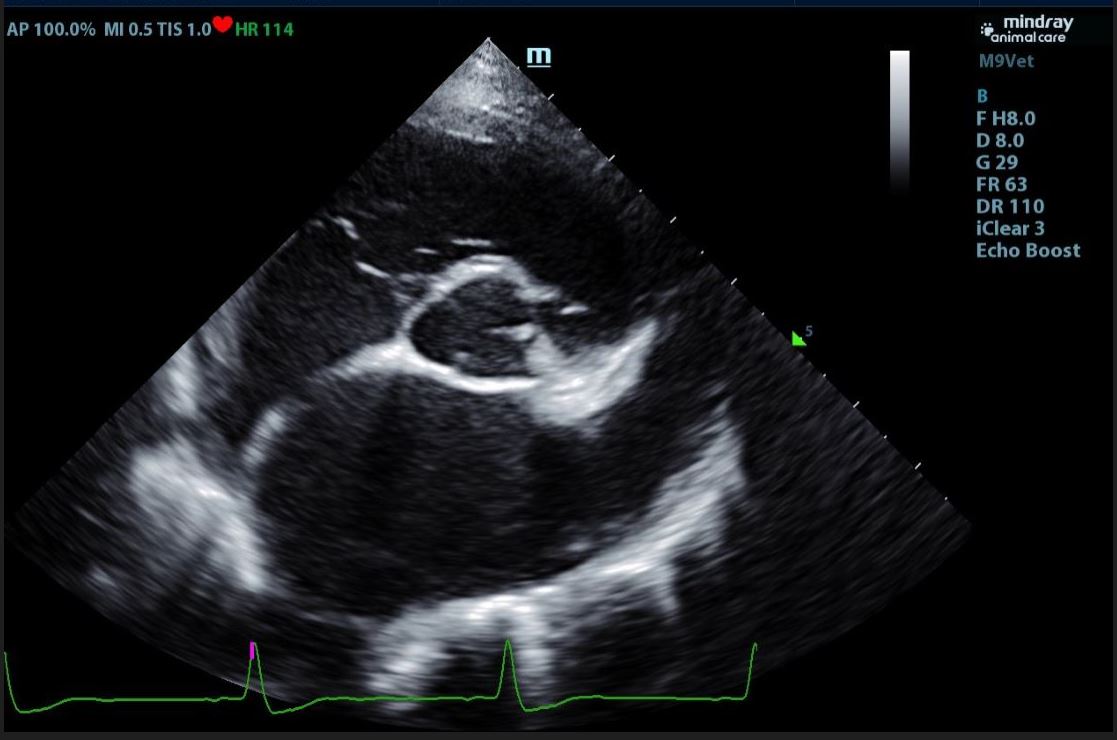

Echocardiograms

Veterinary echocardiography is a type of ultrasound imaging that focuses on the heart.

Echocardiography assesses the structure and function of an animal's heart. This non-invasive

procedure employs ultrasound technology to produce detailed, real-time images of the

heart's chambers, valves, and blood flow. Echocardiography is essential for diagnosing

and monitoring heart conditions such as heart murmurs, cardiomyopathy, and valve disorders.

It helps veterinarians evaluate the severity of heart disease, guide treatment decisions,

and monitor the effectiveness of therapies, all while ensuring the animal's comfort

and safety.